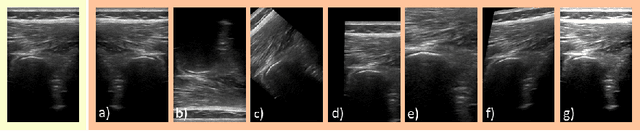

Abstract:Medical Ultrasound (US), despite its wide use, is characterized by artifacts and operator dependency. Those attributes hinder the gathering and utilization of US datasets for the training of Deep Neural Networks used for Computer-Assisted Intervention Systems. Data augmentation is commonly used to enhance model generalization and performance. However, common data augmentation techniques, such as affine transformations do not align with the physics of US and, when used carelessly can lead to unrealistic US images. To this end, we propose a set of physics-inspired transformations, including deformation, reverb and Signal-to-Noise Ratio, that we apply on US B-mode images for data augmentation. We evaluate our method on a new spine US dataset for the tasks of bone segmentation and classification.